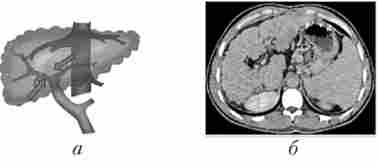

надпечінкова форма портальної гіпертензії обумовлена тромбозом печінкових вен (хвороба Кіарі, рис. 17.2) або нижньої порожнистої вени на рівні печінкових вен (синдром Бадда - Кіарі), здавленням її пухлиною, рубцями.

Надпечінкова форма портальної гіпертензії (мозаїчне накопичення контрастного препарату в збільшеної печінки при прохідною ворітної вени і відсутності візуалізації печінкових вен)

Мал. 17.2. Надпечінкова форма портальної гіпертензії (мозаїчне накопичення контрастного препарату в збільшеної печінки при прохідною ворітної вени і відсутності візуалізації печінкових вен):

а - схема; б - комп'ютерно-томографична ангіограма